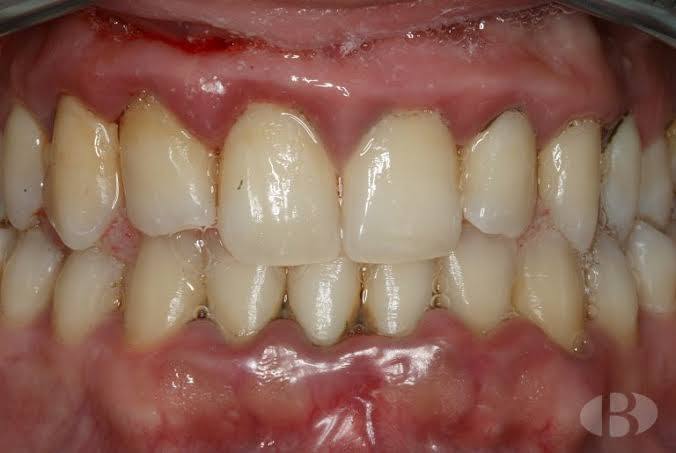

mesa de trabajo 2

Gengivitis